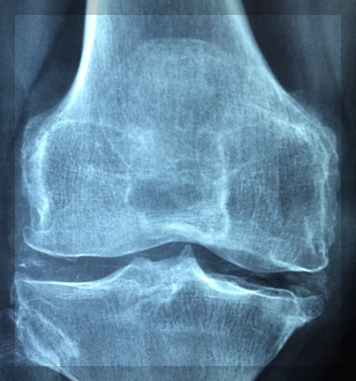

퇴행성 관절염

손가락 관절도 다른 관절과 마찬가지로 노화로 인해 닳아지게 됩니다. 닳아진 관절은 통증과 부종, 뻣뻣함을 유발할 수 있습니다.